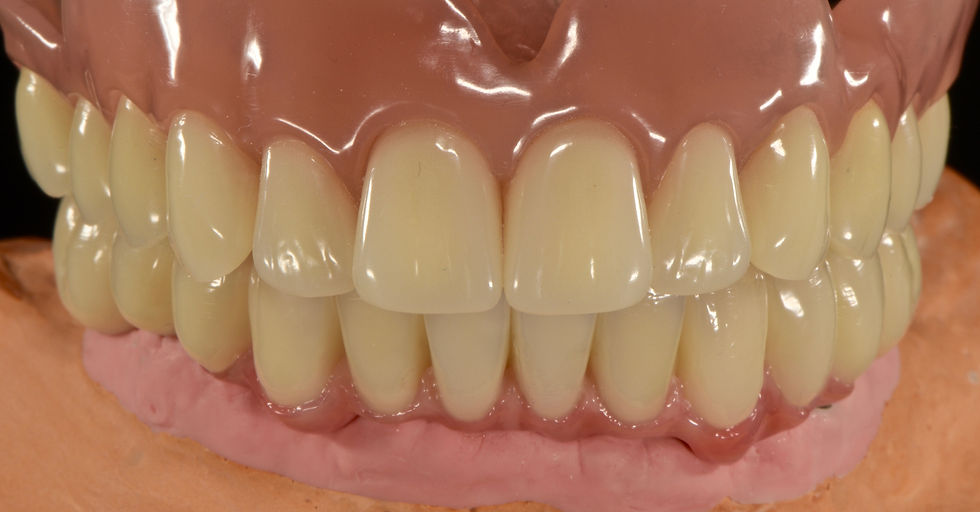

Finalizzation of the upper overdenture and the lower Toronto Bridge in cobalt chrome and molded composite

Details of the lower Toronto bridge

Delivery of both final prosthesis